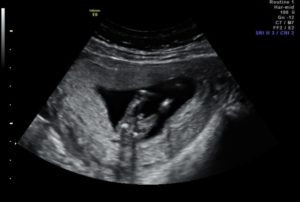

На УЗИ, которое проводят на 15-й неделе беременности будущей матери видно, как активно двигает малыш ручками, ножками. Этот срок характеризуется усиленным развитием мышечной системы.

При удачном расположении плода врач-сонолог может сказать пол ожидаемого малыша. УЗИ на 15-й неделе позволяет проследить за активностью ребенка.

На экране же малыш выглядит длиною около пальца. Если выполняют 3D УЗИ, то на экране видно недовольство крохи, которое проявляется при нажатии на живот датчиком. Ребенок может хмурить бровки, хвататься за пуповину, активнее двигаться.